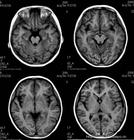

一般头部CT扫描可见梗死或出血性改变。梗死常为多发性的,以额、颞、顶叶、枕叶、基底节区、丘脑等处多见,半数病人可合并额叶萎缩。出血者可以是脑叶出血、基底节出血或蛛网膜下腔出血,而高

血压引起的脑出血多位于基底节区。脑出血的患者也可同时发现梗死灶和(或)脑萎缩。

6.CT扫描 继发脑梗死者可见血管分布相符的低密度区。蛛网膜下腔出血者可见密度增高或血肿形成。

2、头颅CT和MRI并不一定都有异常改变

很多病人甚至不少医生都错误地认为只要头颅CT或MRI正常就没有问题了,其实对烟雾病诊断来讲并非如此。烟雾病的病变最早发生在脑底动脉环,动脉并不是在短时间内从狭窄发展到闭塞,通常是经过了相当长时间,短则数年长则数十年,因此,病人只有轻微症状时就已经有明显的脑动脉狭窄或闭塞,但此时头颅CT可能是正常的,而且,如果没有经验或不仔细观察,临床医生还会忽略头颅MRI-T2相上所显示的颅底大动脉血管稀少及脑基底部血管流空影的增多。有的医生给病人反反复复做了很多次头颅CT和头颅MRI检查,但就是没有检查过一次脑动脉,从而导致症状较轻的烟雾病患者长期得不到诊断。